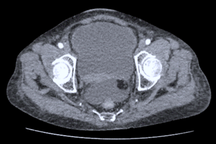

Kết quả thăm khám tại bệnh viện cho thấy bệnh nhân bị vỡ bàng quang, trong ổ bụng nhiều dịch kèm nước tiểu và máu cục. Anh được chẩn đoán chấn thương bụng kín vỡ bàng quang trong phúc mạc và có chỉ định phẫu thuật cấp cứu.

Sau phẫu thuật, sức khỏe của bệnh nhân ổn định (Ảnh: BVCC).

Bệnh nhân được thực hiện phẫu thuật nội soi khâu vỡ bàng quang. Trong quá trình phẫu thuật, các bác sĩ phát hiện thêm tổn thương rách thanh cơ ruột non nên đã tiến hành khâu lại. Hiện tại, sau 2 ngày phẫu thuật sức khỏe bệnh nhân đã ổn định.